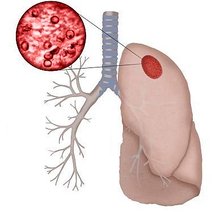

白肺(White lung)是一种临床综合症,其特征是重度肺炎患者的肺部积累了大量渗出物,影响多个肺叶,使肺部影像学检查呈现出大范围的白色区域。病因多为新型冠状病毒感染、细菌性肺炎、中东呼吸...

[最佳答案] 白肺是放射学名词,所谓白肺是指胸片或者CT上弥漫的高密度影,使得片子看不到肺纹理。导致白肺发生的原因很多,常见的大叶性肺炎、肺水肿,或者是病毒性肺炎比如SARS,以及流感、病毒引起的肺炎都会导致白肺。 至于能不能治愈要根据疾病的不同来决定, 白肺是放射学名词,所谓白肺是指胸片或者CT上弥漫的高密度影,使得片子看不到肺...

白肺症状及治疗方案1.白肺症状简介及病因白肺是一种常见的肺部疾病,又被称为白塞病或肺泡蛋白质沉积症。其主要病因是肺部受到损害,导致肺组织中蛋白质沉积,影响正常呼吸功能。白肺症状包括

产生:白肺是一种常见的肺部疾病,通常是由细菌感染引起的。暴露在细菌性感染源,如病人、空气中的细菌等环境中,人体的免疫系统受到损害,细菌便会进入肺部并繁殖,导致白肺的发生。治疗方案:一、治疗目标1.清除体内感染细菌2.缓解